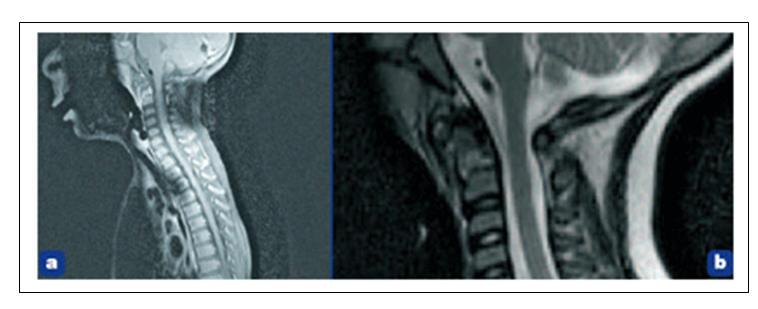

L’article relate la recherche diagnostique qui se conclue sur une spondylodiscite cervicale atlo-axoïdienne, sans avoir retrouvé le moindre germe, et avec l’appui d’un cliché de son IRM cervicale que l’on peut visualiser ci-dessous, puis agrandie.

La scintigraphie osseuse montre une hyperfixation tardive se projetant au niveau des vertèbres cervicales C1 – C2 (figure 2), mais ne permet pas de trancher entre l’hypothèse traumatique et la spondylodiscite. C’est l’IRM cervicale qui apporte le diagnostic de certitude (figure 3), confirmant un aspect de spondylodiscite cervicale C1–C2, sans épidurite ni signe d’atteinte médullaire.

Figure 3. IRM cervical en coupe sagittale T1 avec injection (a) et en T2 avec agrandissement (b). On note un hyposignal de l’odontoïde en T1 avec rehaussement périphérique lié à l’injection de gadolinium ainsi qu’un léger hyper signal T2.